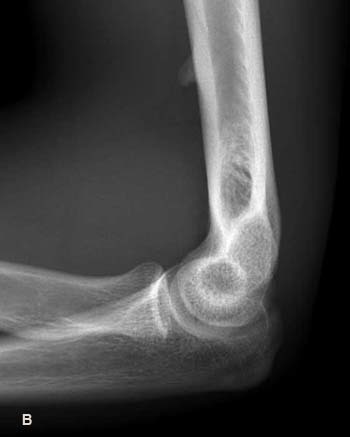

Little League elbow

• avulsion frature of the medial epicondyle